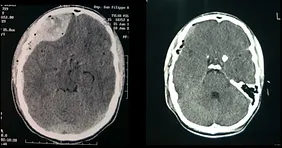

Ematoma Subdurale Cronico

Ematoma Subdurale Cronico Fotografia Stock Immagine Di Neurochirurgia

Tac Del Cervello Con Ematoma Subdurale Fotografie Stock E Altre Immagini Di Cervello Umano Istock